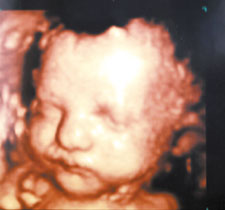

التصوير رباعي الأبعاد يكشف عن تشوهات الجنين مركز الاشعة وسونار حكيم اوغلو

جهاز رباعي الأبعاد لاحظ تعابير وجه الجنين Youtube

ايكو رباعي مباشر للجنين Youtube